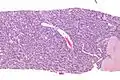

Low mag.

Low mag. High mag.